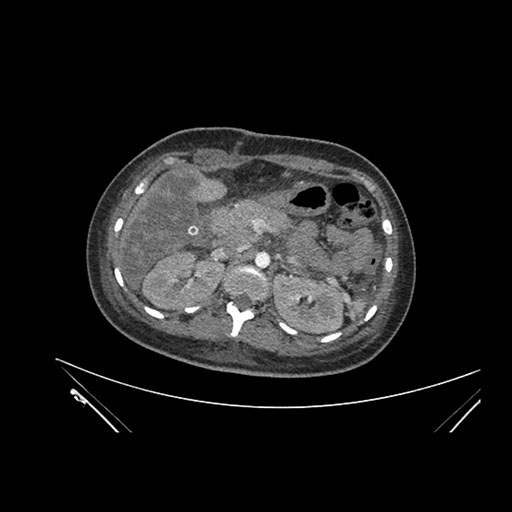

Axial Arterial

Axial Venous